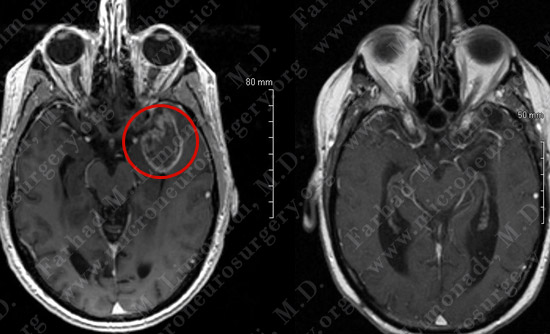

Imaging

- He underwent a thorough evaluation by his neurologist including an MRI scan of the brain.

- On neurological examination, he had no deficit.